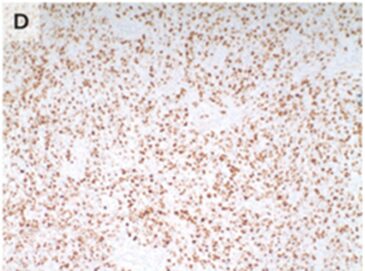

切開生検施行。組織病理学的検査により、ミオゲニン(myogenin)陽性の青色小細胞の密なシートが確認された。

「胎児性横紋筋肉腫」(小児で最も一般的な原発性眼窩悪性腫瘍)と診断された。